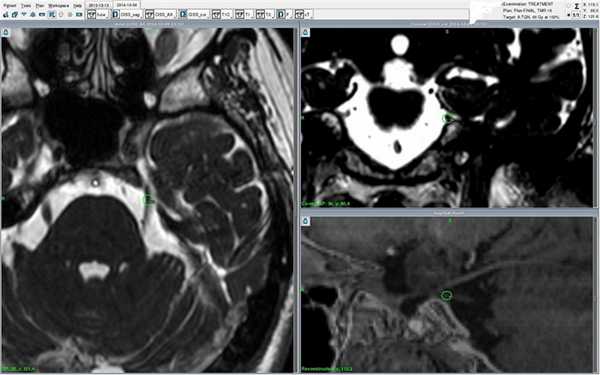

Пациентка М., 32 года, диагноз "кавернозная ангиома правого полушария мозжечка". Выполнена радиохирургия на Гамма-ноже. Справа - контрольное МРТ через 14 месяцев после лечения - достигнут полный регресс образования.

После одного сеанса в течение 5-90 месяцев достигается облитерация мальформации (заращение полости соединительной тканью), в 70% полость полностью закрывается и вероятность кровоизлияния снижается до нулевой.